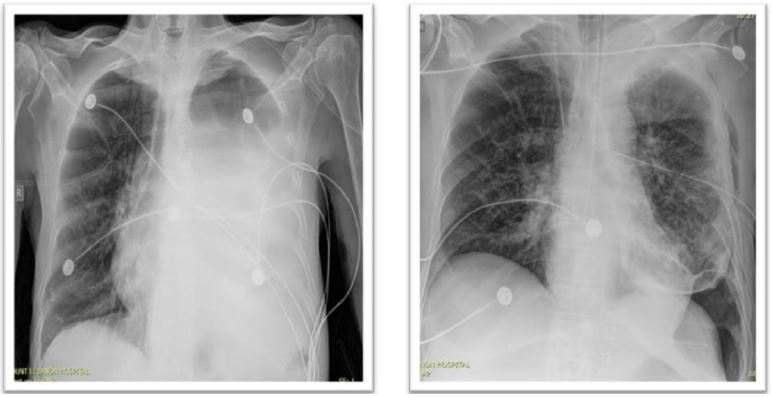

The patient was transferred to the ICU post-Operative. Extubated day one post-Operative, hemodynamically stable with 5 L O2 NC requirements (Figure 3). Diet resumed on day two post-Operative. Intra-Operative cultures returned positive for Ecoli ampC and targeted anti-biotherapy started. During his stay patient presented multiple respiratory complications that required a new chest tube placement, bronchoscopy, CT guided drainage of a left pleural effusion.

Figure 3: Chest X-ray pre-OP vs day 1 post-Op.

On the day of discharge, the patient had PUS draining from the chest tube. A CT Chest was done and showed increased air component and decreased fluid

Amount of a previously described loculated pleural effusion with parietal and visceral pleural thickening (Figure 4). Hospital stay was complicated by organized empyema of the left lung, managed with left posterolateral thoracotomy, left lung decortication, and empyema drainage. The patient was then extubated on day 2 post decortication. Re-intubated 10 days after for respiratory failure and then passed away two weeks later from cardio respiratory arrest.

Figure 4: Ct, transversal view: left pleural effusion with parietal and visceral pleural thickening.